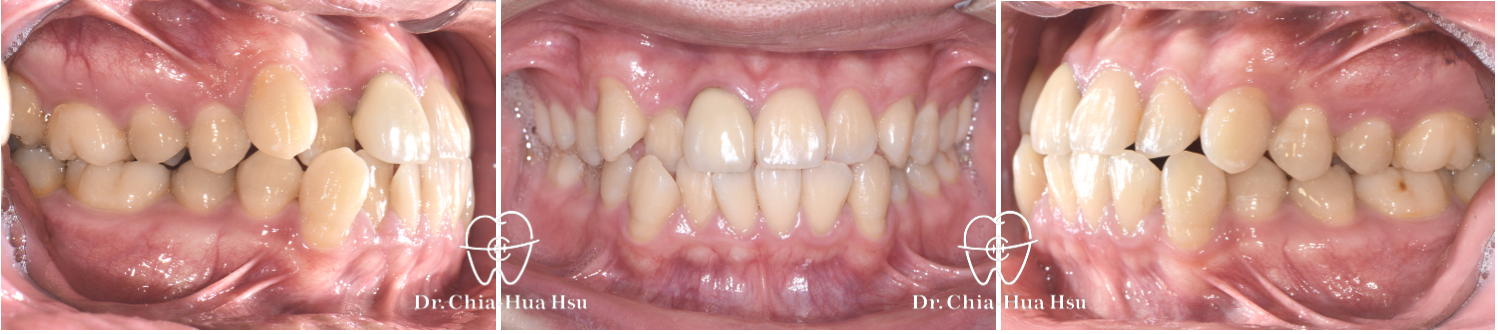

前牙錯咬、齒列擁擠

• 病患主訴:牙齒凌亂擁擠、笑起來不好看。

• 問題分析:患者是標準的骨骼一類咬合(Skeletal Class I)伴隨齒列擁擠以及前牙錯咬。

• 治療方式:拔除四顆小臼齒,使用傳統金屬矯正器將牙齒排列整齊、咬合緊閉。

• 治療時間:1 年 10 個月。

• 治療結果:齒列排齊,笑容更燦爛。

治療前

治療後